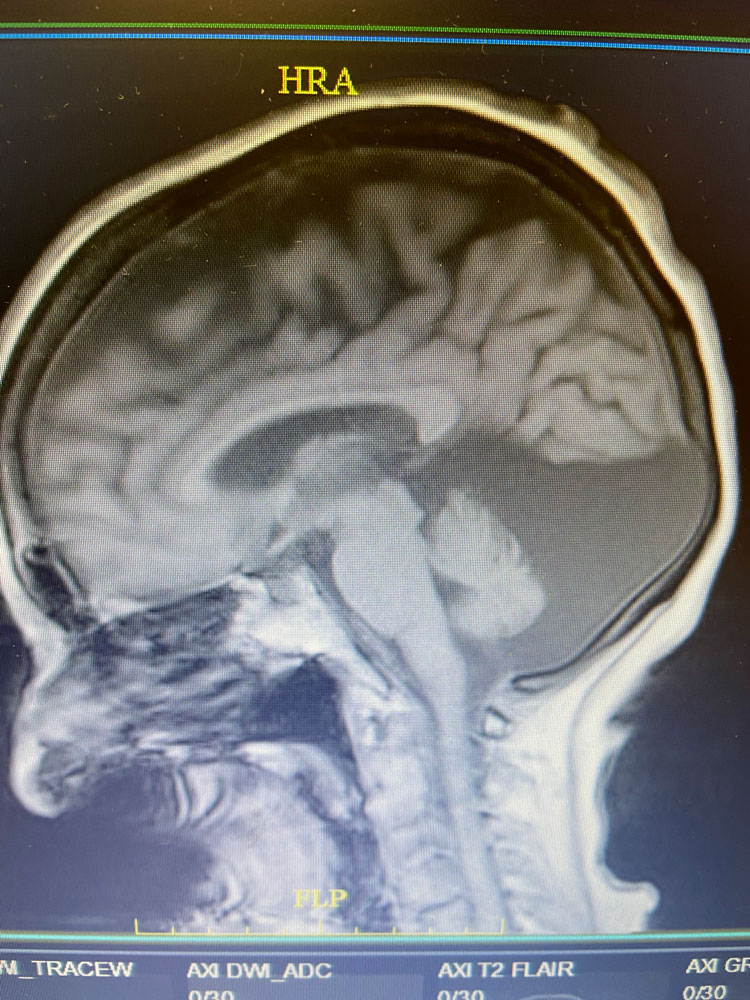

Imaging:

The Brain MRI showed a very large arachnoid cyst in the posterior fossa. Arachnoid cysts are collections of cerebrospinal fluid (csf) that are usually long-standing asymptomatic abnormalties. They are generally thought to be congenital. Arachnoid cysts generally do not require any treatment, except in rare instances.